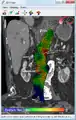

An aneurysm ruptures if the mechanical stress (tension per area) exceeds the local wall strength; consequently, peak wall stress (PWS),[30] mean wall stress (MWS),[31] and peak wall rupture risk (PWRR)[32] have been found to be more reliable parameters than diameter to assess AAA rupture risk. Medical software allows computing these rupture risk indices from standard clinical CT data and provides a patient-specific AAA rupture risk diagnosis.[33][34][35] This type of biomechanical approach has been shown to accurately predict the location of AAA rupture.[34][35][36]

Biomechanical AAA rupture risk prediction